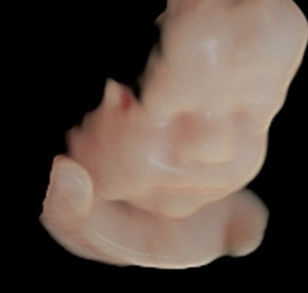

26 Weeks 1 Day Pregnant

26 Weeks 3 Day Pregnant